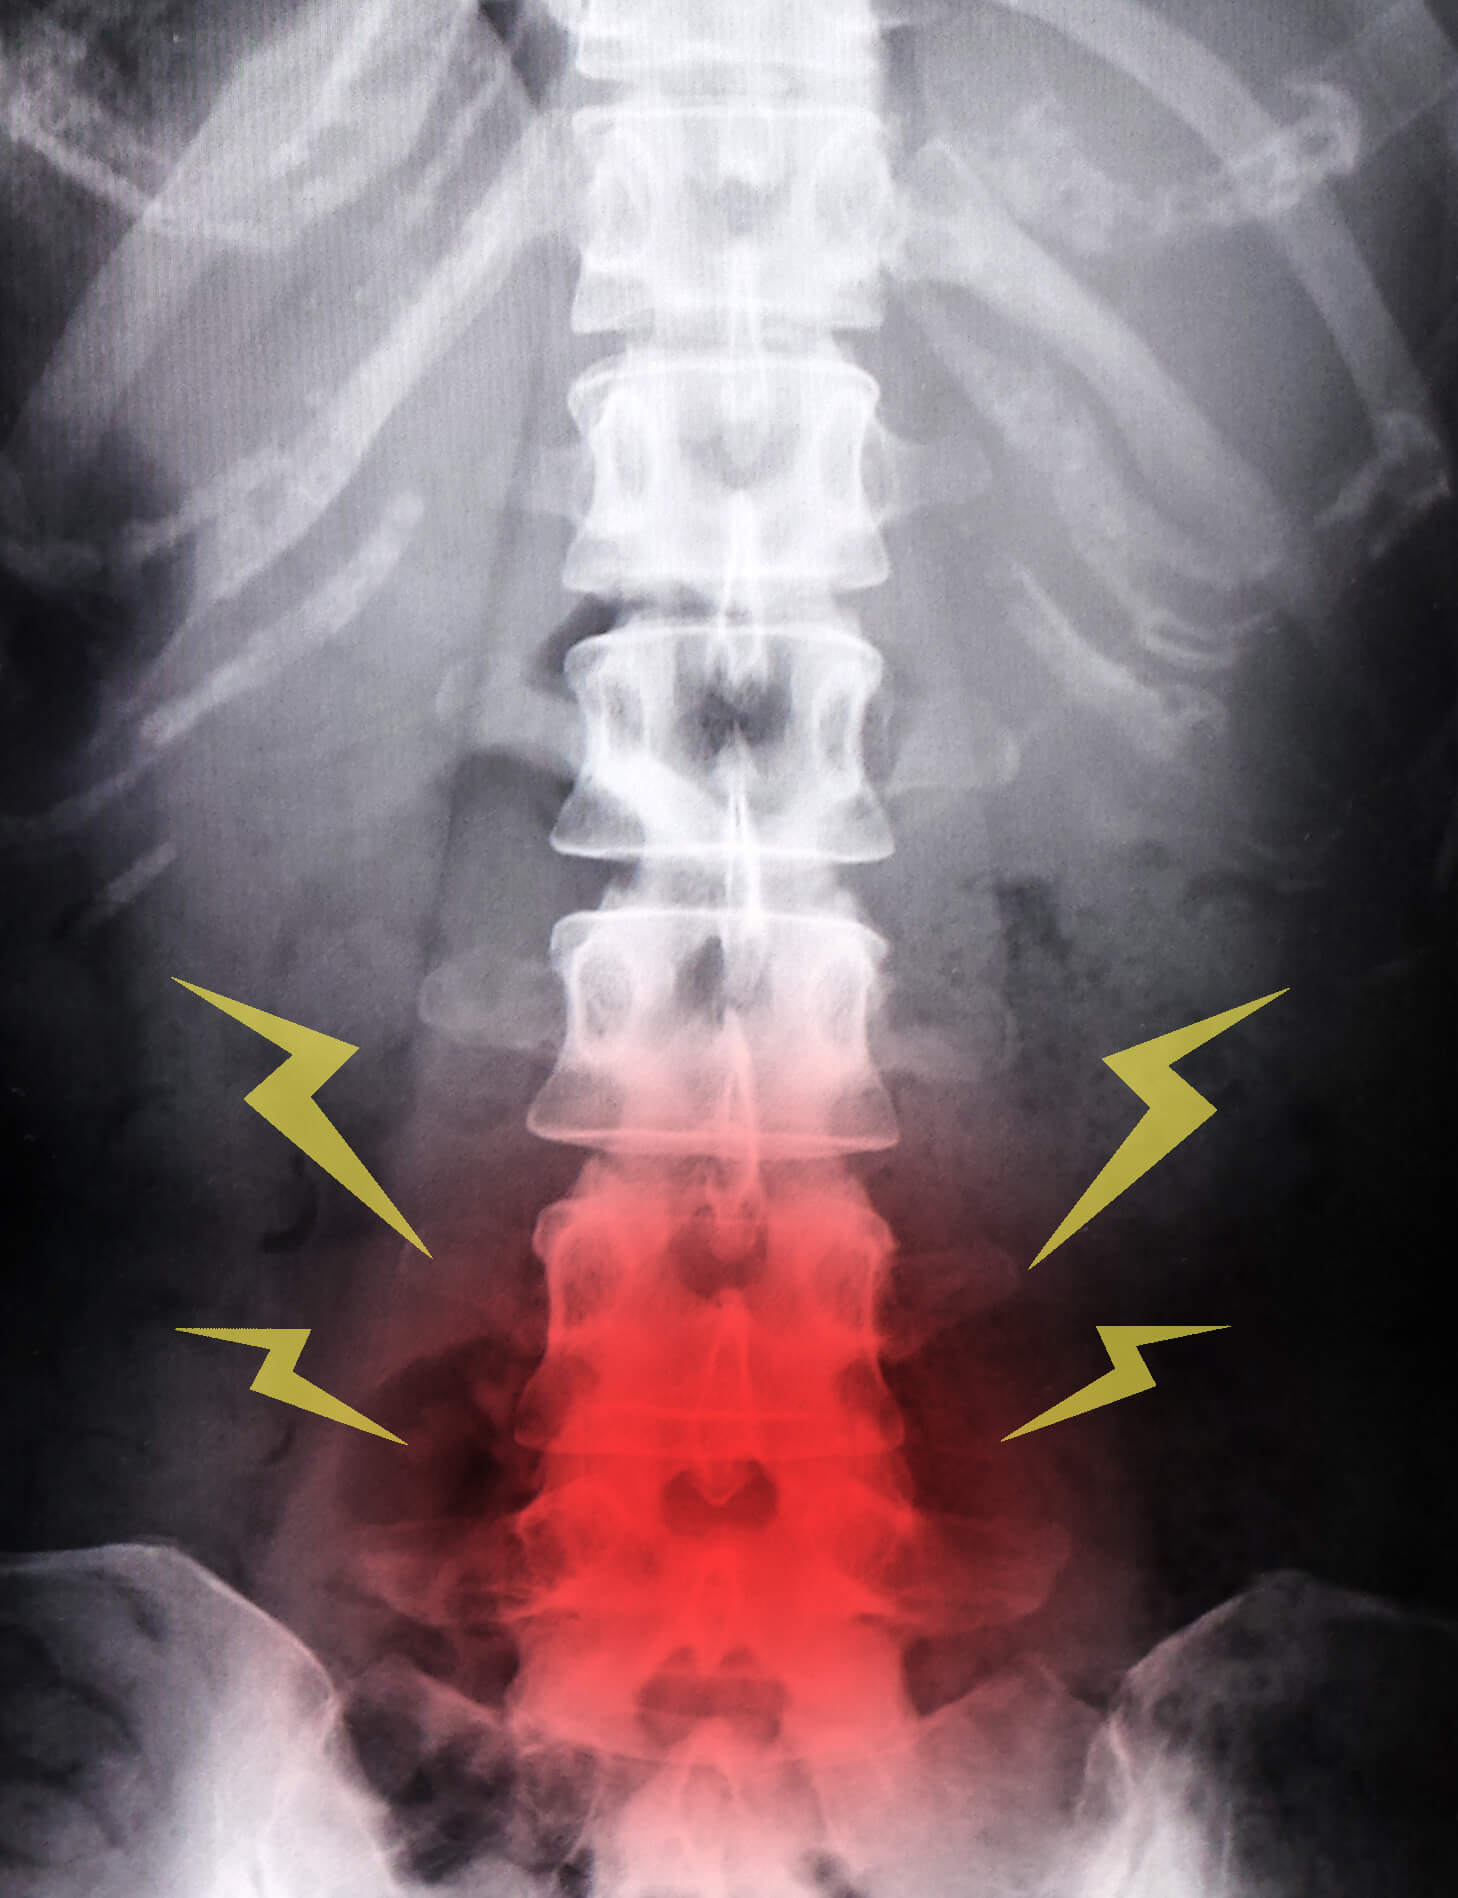

骨粗鬆症と治療の継続です。

骨粗鬆症という病気は

それ自体は症状がない事が多いため

しかし、一度骨折を起こしてしまうと

様々な日常生活における障害が起きてしまいます。